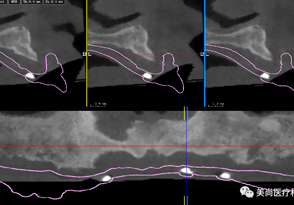

A.将CBCT数据导入软件中

B.绘制下颌神经管

C.添加模型数据

D.图像拟合

F.选择牙位添加种植体

G.选择合适的导环全程或者定位完成植体设计